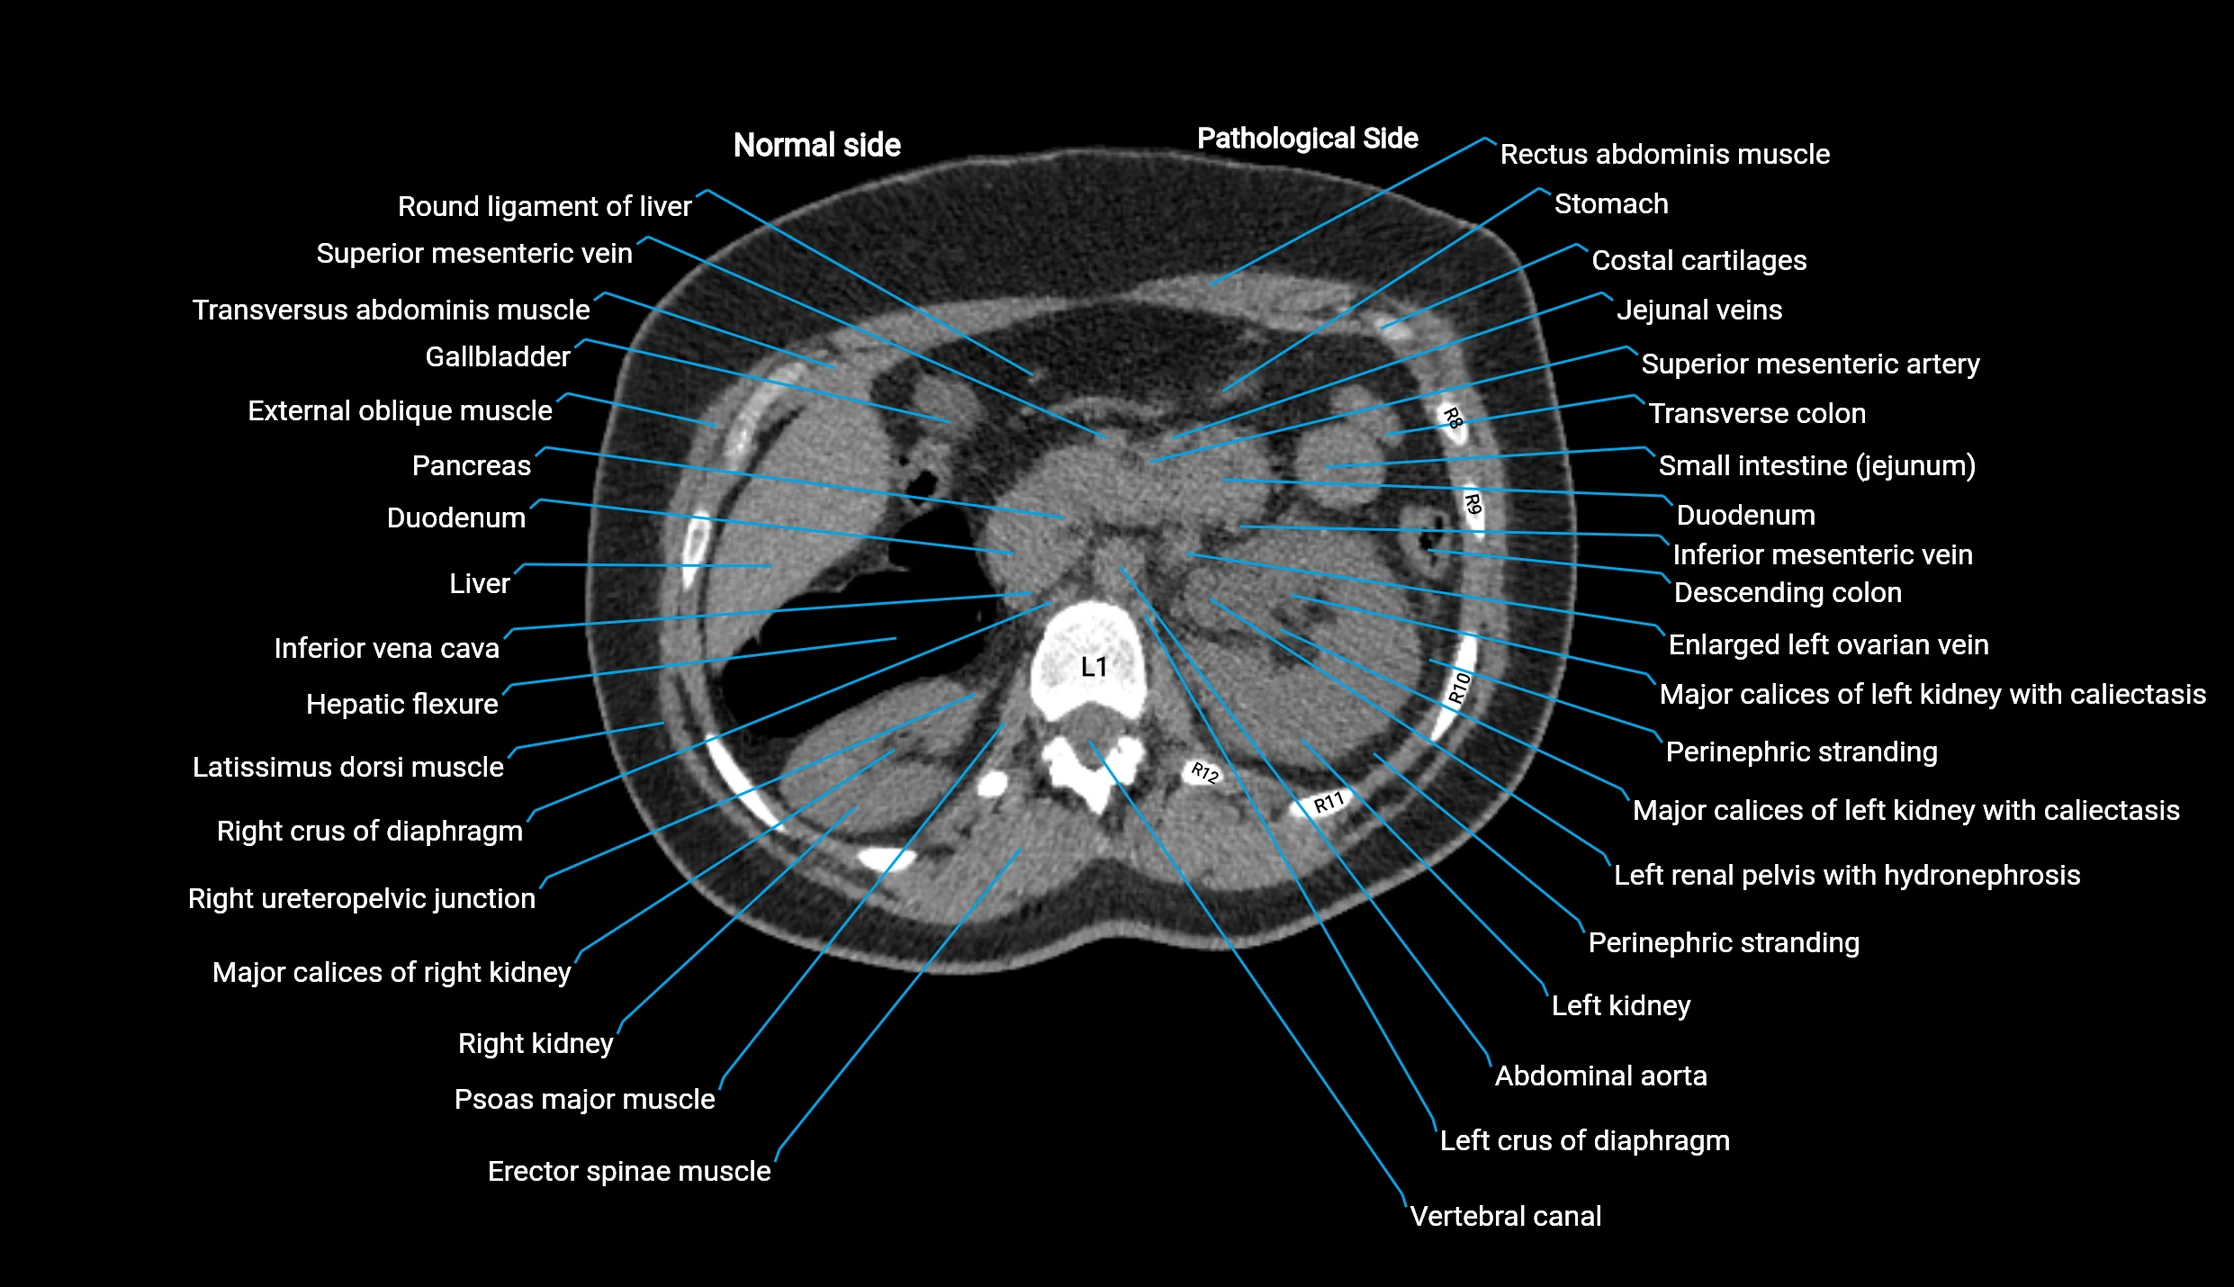

CT image

image